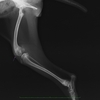

触診とレントゲン写真で前十字靭帯断裂と診断しました。

左後肢の脛の骨が右足と比べて前方に変位しているのがわかります。

術後レントゲンです。